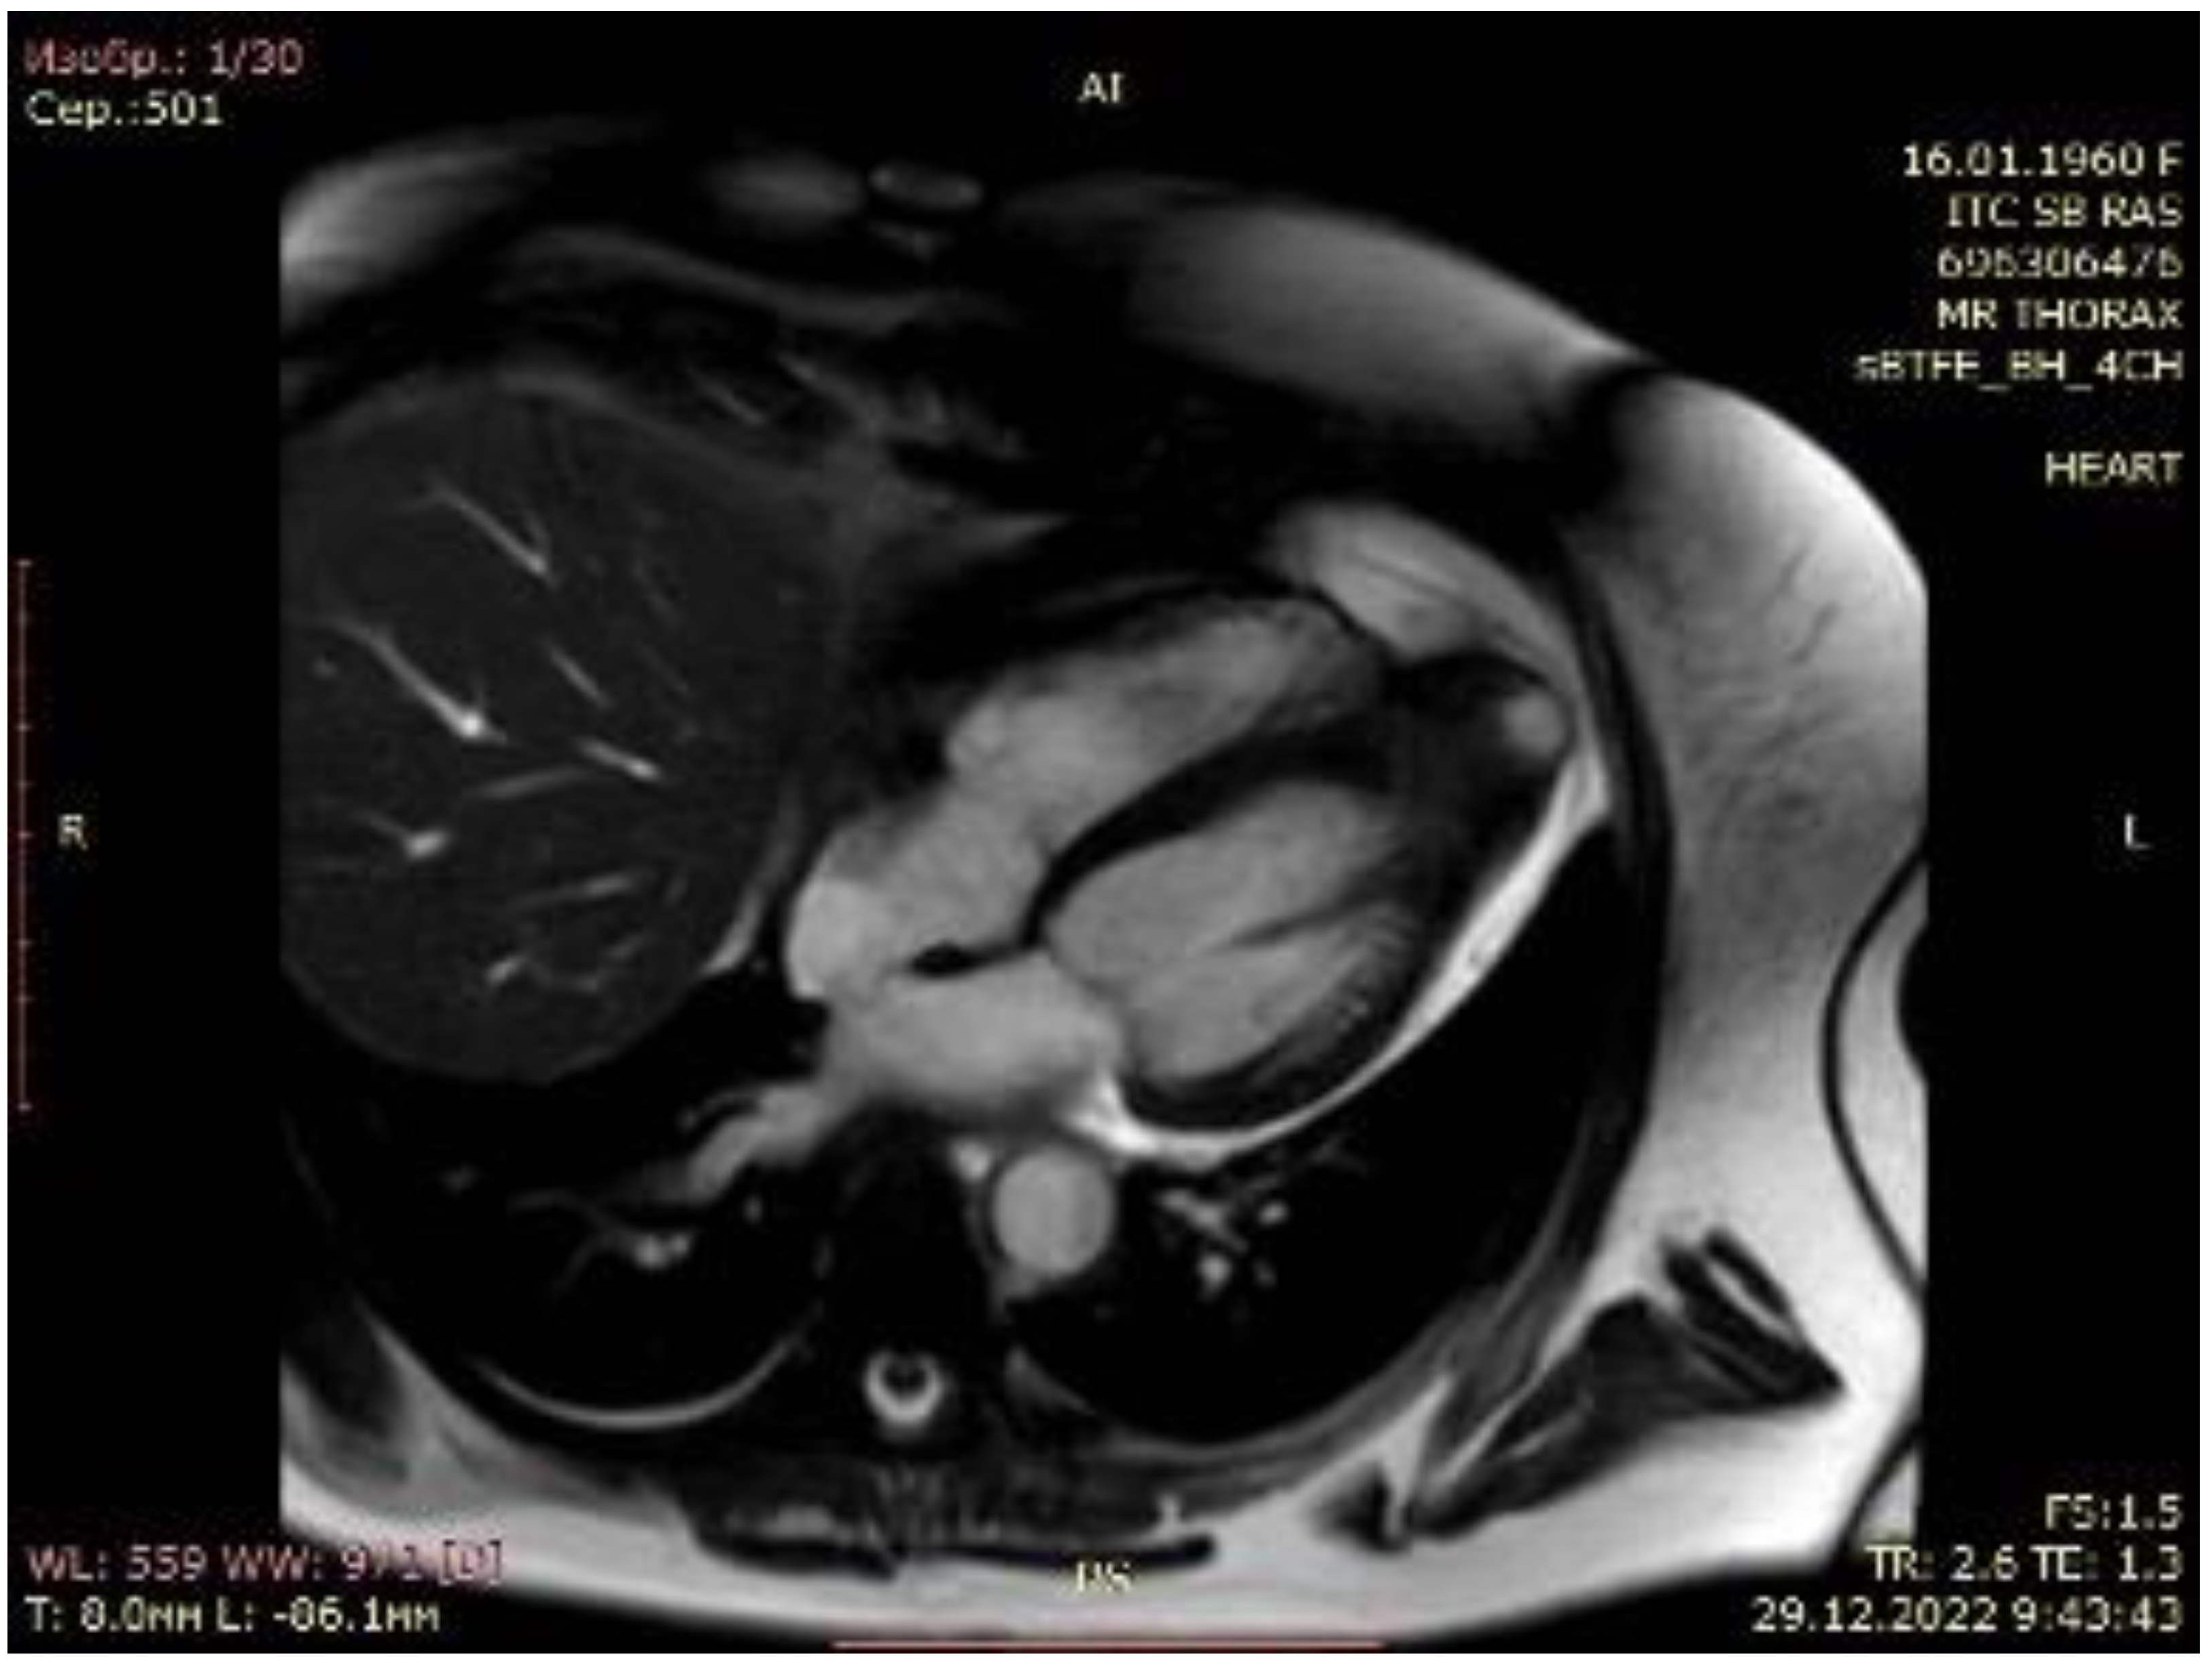

2.1. Case Scenario